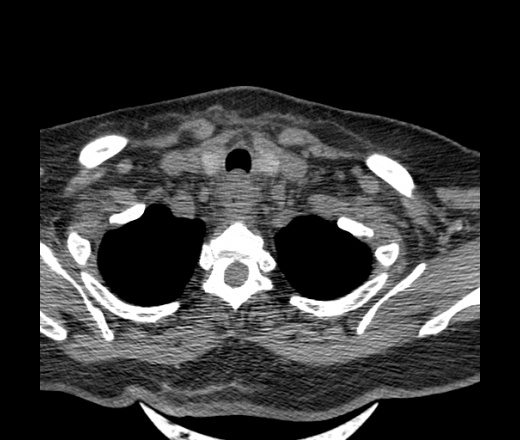

Женщина поступила в х/о спустя 4 дня после того как при употреблении карася подавилась костью.

Наличие газа в средостении на протяжении тел С2-С6 (медиастинальна эмфизема); рыбная кость на уровне тела С6.

При всем уважении, но говорить о медиастинальной эмфиземе, оценивая мягкие ткани шеи, как-то слишком резко. На мой взгляд, это ретрофарингеальное пространство.

Эвакуировали почти 100мл гноя. Но кость не смогли найти. Думаю что она даст дальнейшее ослоднение. Эндоскопически за черпалонадгортаной звязкой не смогли зайти в пищевод, все мягкие ткани отечные, просвет пищевода сдавлен. По всей видимости параэзофагеальная клетчака тоже задействована. Эмпиема, если ее можно так назвать, незнаю как правильно дошла до уровня яремной вырезки. Чем закончиться напишу. Ждем медиастинита.

Флегмона заглоточного пространства шеи, только операция, флегмоны вскрывают. Риск медиастинита.

Согласен с Вами; конечно, наличие газа в клетчатке ретрофарингеального пространства (затмение с опечаткой..). К сожалению, процесс "продвигается" к медиастиниту. Но почему никто, не отмечает наличие рыб. кости; или это для Всех очевидно?

Так вы уже отметили. Хотя ориентировал бы не скелетотопически, а на перстнечерпаловидный сустав.

Кость то мы сразу выявили, размеры где то 17*2мм, но ее так и не получается найти в этой каше